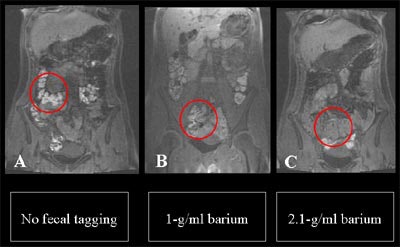

![]() |

| Signal intensity (SI) of fecal material was reduced in response to various tagging protocols. 100% refers to Micropaque formula, which contains 1 g barium-sulfate per ml; 210% refers to Maxibar formula, which contains 2.1 g barium-sulfate per ml. Chart courtesty of Dr. Thomas Lauenstein. |